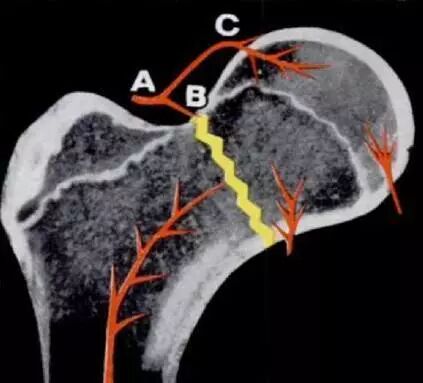

未成年人的股骨颈骨折多由巨大的暴力导致,发生率不及1%。虽然在临床中并不常见,一旦发生股骨颈骨折,多伴随股骨头坏死、骨不连、骨骺早闭、髋内翻等并发症,严重影响患儿的生长发育与生活学习。其中,股骨头坏死是未成年人股骨颈骨折后最为常见的并发症,发病率平均为23%(图1)。由于未成年人股骨近端血运与骨骺发育不全,一旦发生坏死多表现为大面积的坏死,如无有效的干预,必然导致灾难性的后果(图2)。

图2:未成年人股骨颈骨折血运破坏与骨骺的关系 Ratliff, A. H. (1962). "Fractures of the neck of the femur in children." J Bone Joint Surg Br 44-B: 528-542.